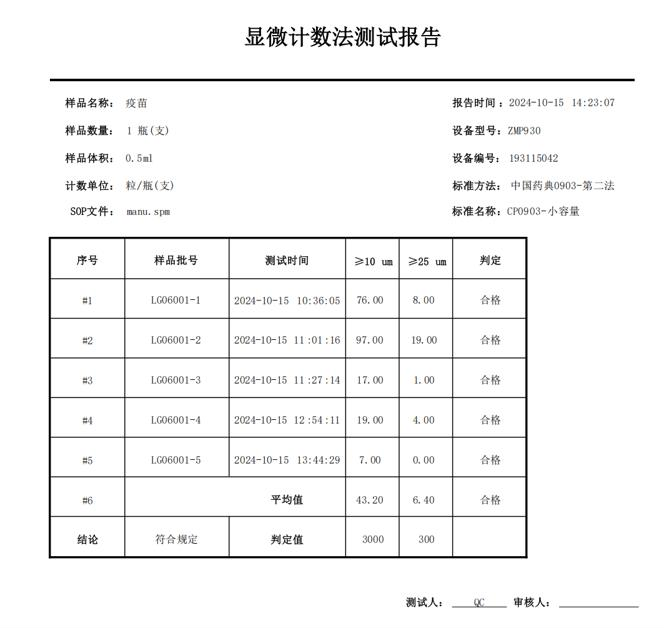

3.報告輸出標準化:可自動生成符合 2025 版藥典 CP0903、USP788 等標準的中英文報告,直接呈現 “≥10μm、≥25μm 微粒計數” 等關鍵指標,無需人工二次整理,減少數據轉錄誤差。